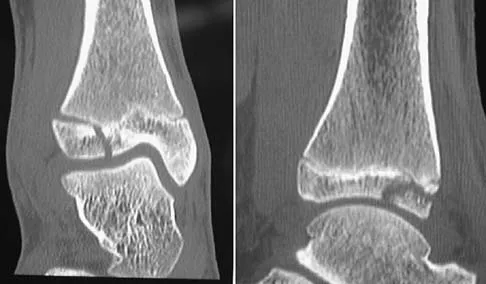

A 50-year-old laborer sustained an isolated closed injury to his heel after falling 11 feet off a wall. A radiograph and a CT scan are shown in Figures 4a and 4b. To minimize the patient's temporary disability and allow him to return to work most rapidly, management should consist of